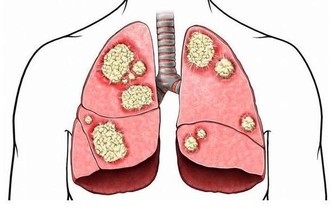

A. 血脂過高:

長期血脂過高, 易引起血管壁硬化,

加上血脂過高, 血液粘稠, 血流變慢,

細胞所得到氧氣養料減少, 導致麻木.

B. 糖尿病人:

血糖維持較高水平, 長久以往,

對人體血管, 神經造成極大傷害, 血管硬化, 神經變性.